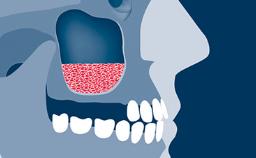

Digitally Guided Sinus Floor Elevation

In this short microlearning module on digitally guided sinus floor elevation, we delve into a specialized aspect of the digital workflow for implant-guided surgery, focusing on the use of digital guides in the sinus floor elevation technique.

- understand the rationale and advantages of utilizing digital guides for sinus floor elevation (SFE)

- describe the indications for digital guides in SFE

- define the manufacturing process of digital guides for SFE

- explore the intraoperative use of digital guides in SFE